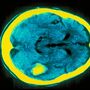

Cientistas transformaram células da pele em células estaminais que destroem os cancros do cérebro chamados glioblastomas

A técnica, anunciada na revista Nature Communications, pode levar, pela primeira vez em 30 anos, a tratamentos mais eficazes da doença que tem uma taxa de sobrevivência para lá dos dois anos de apenas 30 por cento.